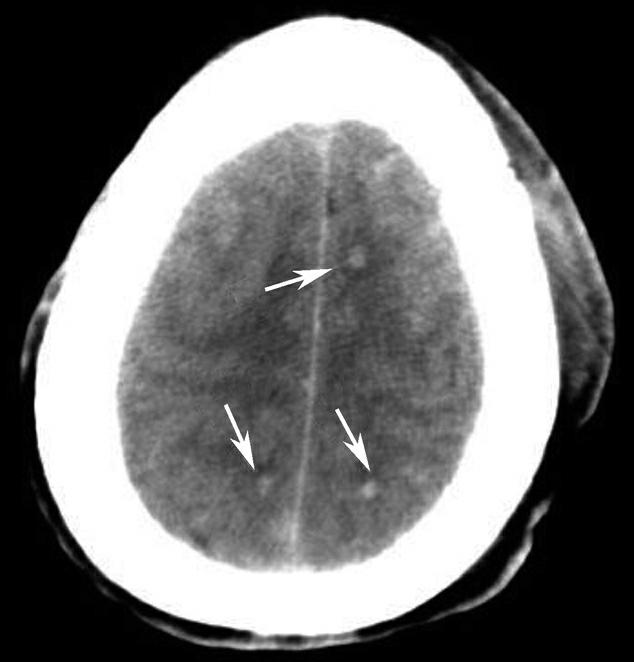

Alberta卒中项目早期CT评分(Alberta stroke program early CT score,ASPECTS)是一种评价急性缺血性卒中患者大脑中动脉供血区早期缺血性改变的简单、可靠、系统化的方法,是常用的脑卒中评定量表之一,可对缺血性病变快速进行半定量评价,有助于判定溶栓效果和远期预后。该评分主要基于CT平扫,具体分区如下(图1-2-76)所示,即选取大脑中动脉供血区2个层面。分区后共10个区域,每个区域记1分。评分时任何区域只要有低密度灶,则扣除该区域得分。正常脑ASPECTS评分为满分(10分),若MCA供血区广泛梗死累及全部区域时,则ASPECTS评分为0分。

图1-2-76 ASPECTS评分脑组织分区

A.在基底节层面(即丘脑和纹状体平面),分为各级分支M 1 、M 2 、M 3 、岛叶(缩写I)、豆状核(缩写L)、尾状核(缩写C)和内囊(缩写IC)后肢等7个区域;B.在基底节以上层面(基底节层面上2cm),包括M 4 、M 5 和M 6 。